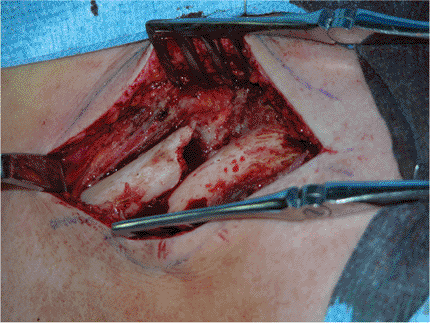

An oblique incision is made along the superior surface of the clavicle.

The skin and subcutaneous tissue are raised as a flap, protecting any

obvious cutaneous nerve branches, and reflected upward allowing the

underlying myofascia to be identified (Fig. 1.7).

This layer, including the deltopectoral muscle attachment, is raised as

contiguous flaps and is preserved so that a two-layered closure can be

Figure 1.8. The fracture site is exposed.